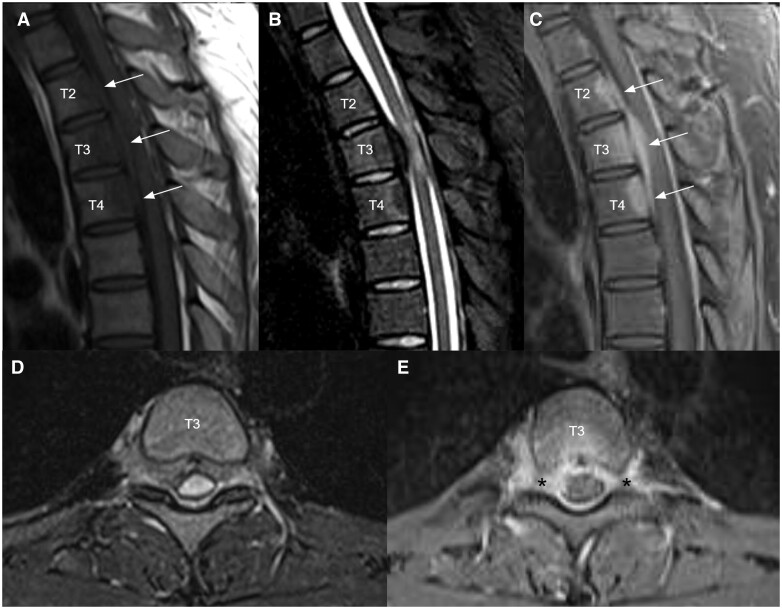

IgG4-related disease is an immune-mediated fibroinflammatory condition. Isolated manifestation in the spine as hypertrophic pachymeningitis is very rare and the mass-like lesion on MRI often mimic tumour or infection. Patients would present with symptoms that result from mass effect or neurovascular compression. Studies showed that serum and CSF IgG4 levels are rarely informative, and therefore, tissue biopsy is crucial for accurate diagnosis. Apart from supporting the diagnosis, MRI is helpful in delineating the extent of disease and follow-up after treatment. A 18F-FDG PET/CT scan is useful in detecting systemic manifestations of IgG4-related disease. Although IgG4-related disease generally responds well to corticosteroid at inflammatory state, relapse is not uncommon. Current treatment strategies for IgG4-related hypertrophic pachymeningitis are high dose corticosteroid therapy and early decompressive surgery to avoid chronic neurological complications. We described a case of a 27-year-old gentleman complaining of lower limb weakness and numbness. MRI showed a mass-like epidural lesion at the thoracic spine causing cord compression. Open biopsy of the epidural mass demonstrated histopathological characteristics of IgG4-related disease. Patient responded well to early surgical decompression of the spinal cord and corticosteroid as evidenced by symptom improvement and resolving mass on subsequent MRI study. However, a follow-up MRI revealed disease recurrence years later.